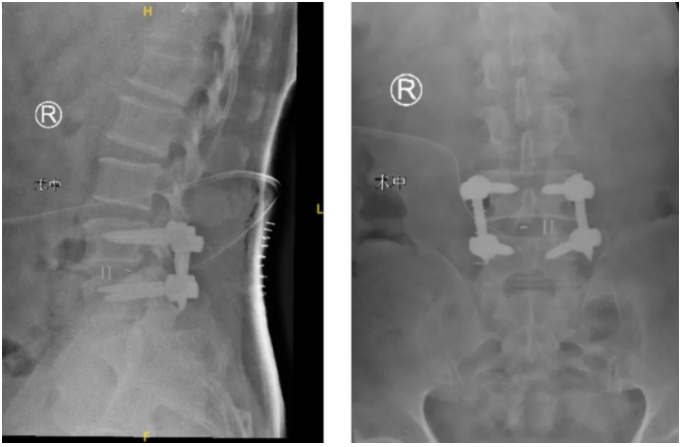

在智能骨科机器人+3D裸眼显微镜的辅助下,王先生的手术很成功,术后皮肤表面只留下了3cm的小切口!

术后